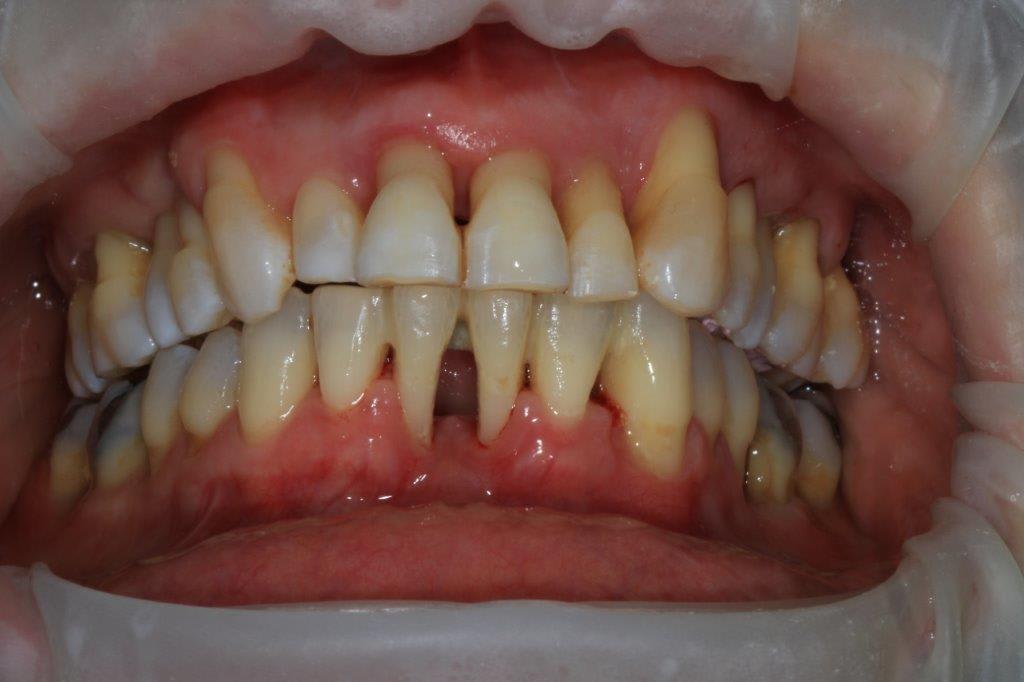

petit boulot de ce jour, "coronoplastie de sauvage", afin d'essayer de supprimer les contacts nocifs... ensuite endo 24/25/26.

en occlusion, ça parait moins destructeur, la suite mardi prochain.

surtout dans des cas comme celui là où il y a des mylolyses bilatérales et une double occlusion.

Sur une occlusion qui ést du genre un coup a gauche , un coup a droite, son calage était au départ sur le secteur incisif.

Elle se servait du bloc ant comme un point d appuis pour se faire sa translation postérieure.

Le fait de ne pas supprimer les décalages de crête, alors que tu lui a enlevé son calage ant , et va faire du bruxisme centré ( serrage ') de compensation sur les crêtes les plus saillantes n ayant plus d engrenement suffisamment stable .

Au't chose , tu as diminué le recouvrement ant , c est bien , mais ce qui n empêche qu il faudrait biseauter les bords livres des incisives du bas et du haut .

Histoire qu elle puisse fermer en venant d une position moins axiale obligatoirement , comme avant . .

Supprimer du recouvrement ne voulant pas forcément dire supprimer du sur guidage .

d ailleurs je soulagerais aussi le verrouillage canin .

Bref on voit mieux sur ces photos que ce sera le haut qu il faudra couronner en fonction du bas qui lui n'est pas dégueulasse .